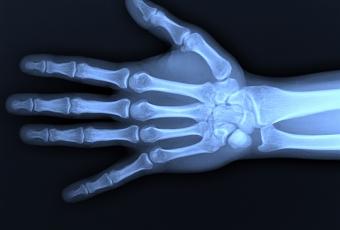

A través de una radiografía se obtiene la imagen de una parte del cuerpo y de los órganos internos que la componen. La parte a radiografiar recibe una mínima cantidad de radiación que se reflejará en una placa fotográfica. Esta radiación penetra con mayor o menor intensidad según el tipo de tejido u órgano de que se trate, identificando tanto pulmones, corazón o riñones como huesos o tumores. El paciente se coloca entre la fuente de radiación y la placa fotográfica. Se trata de una prueba segura y eficaz, tiene un uso diagnóstico previo a la realización de cualquier tratamiento Leer más sobre el artículo "Radiografías en el embarazo"